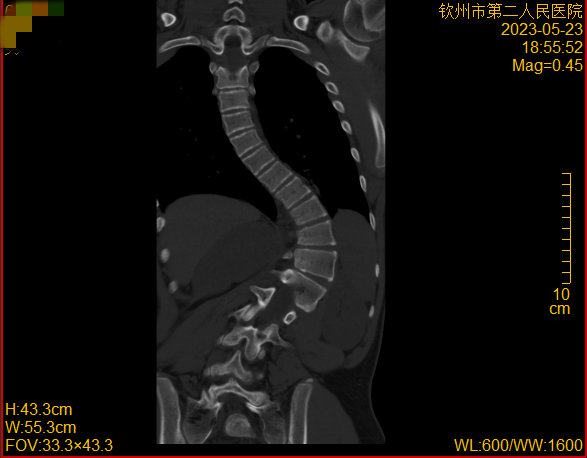

入院骨外科三区(脊髓脊柱外科)后,立即给予完善相关检查,检查结果排除了先天性骨结构异常、脊髓神经等疾病所致脊柱侧弯。结果提示小明患的是:特发性脊柱侧弯!

特发性脊柱侧弯(idiopathic scoliosis)是指一种脊柱畸形,儿童或青少年期间脊柱侧弯达到10度以上即可确立诊断。该疾病常常在儿童或青少年时期发病,如果不及时治疗,会导致脊柱扭曲,造成身体不平衡和心理困扰。

脊柱侧弯也叫做脊柱侧凸,指的是脊柱的一个或数个节段在冠状面、矢状面和水平面上的序列异常,是一种脊柱的三维畸形。通俗来说,正常人的脊柱从后面看是直的,而脊柱侧弯患者的脊柱从正面看是呈字母“C”形或者“S”形的。